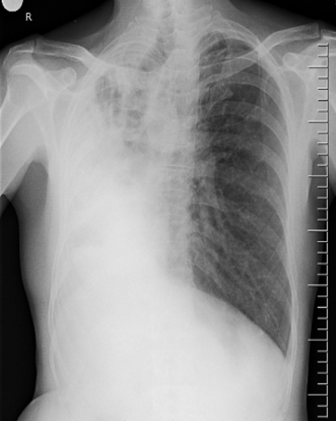

RT. Lung Collapse

The whole hemithorax is opaque. ±Ipsilateral

- There is loss of lung volume.

- Shift of trachea to the to the RT Tracheal_deviation

- Compensatory hyperinflation of left lung

Loss of lung volume do not occur in pneumonic consolidation.